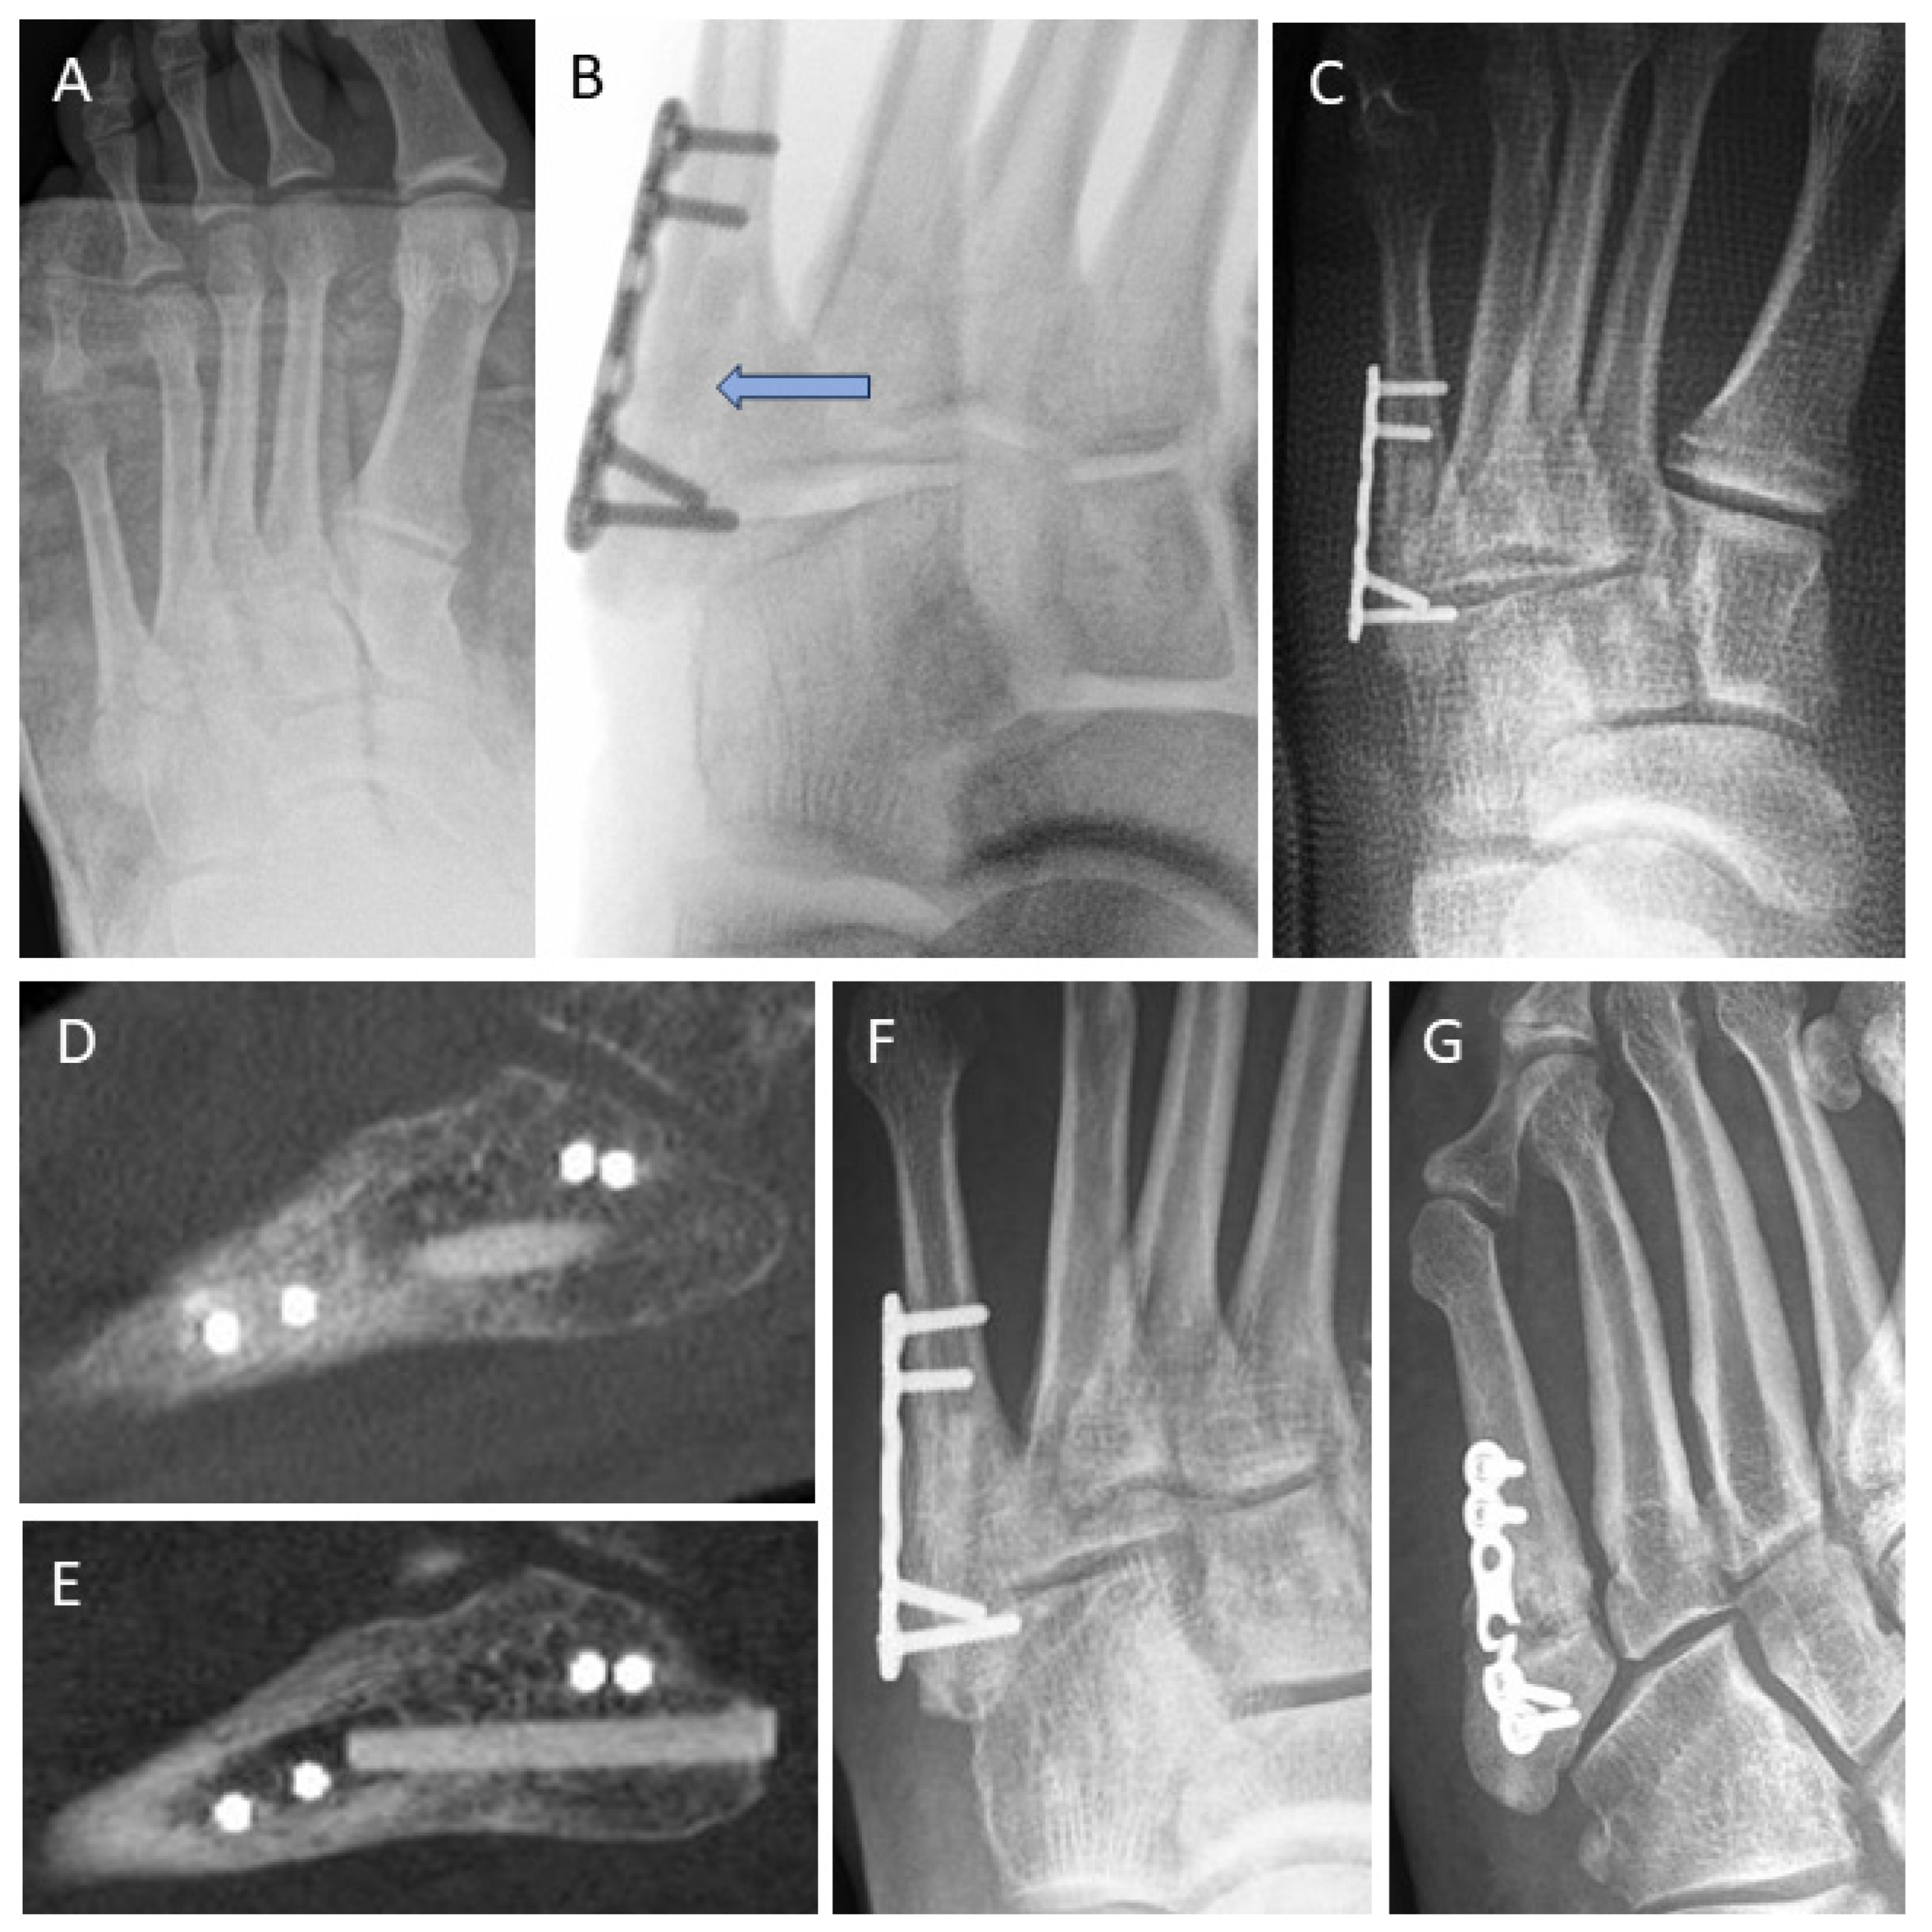

3.4. Examples for Bone Healing

3.6. Radiological Findings of Interest